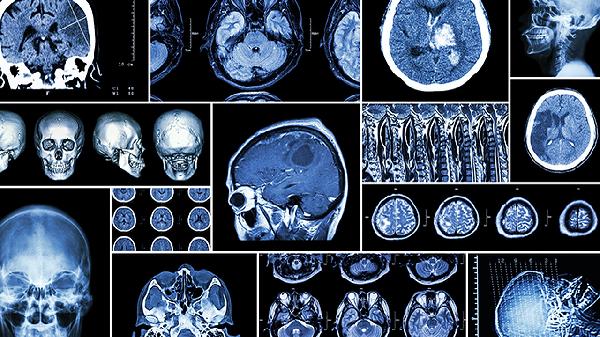

两种强直状态均可出现在意识障碍患者中,但去大脑僵直提示脑干功能受损,预后通常较差。临床检查时可通过疼痛刺激诱发姿势反应进行鉴别,去大脑僵直患者对刺激反应为四肢同步伸展,而去皮质强直患者表现为上肢屈曲与下肢伸展分离。脑电图、头颅CT或MRI等检查有助于明确具体病变部位和性质。